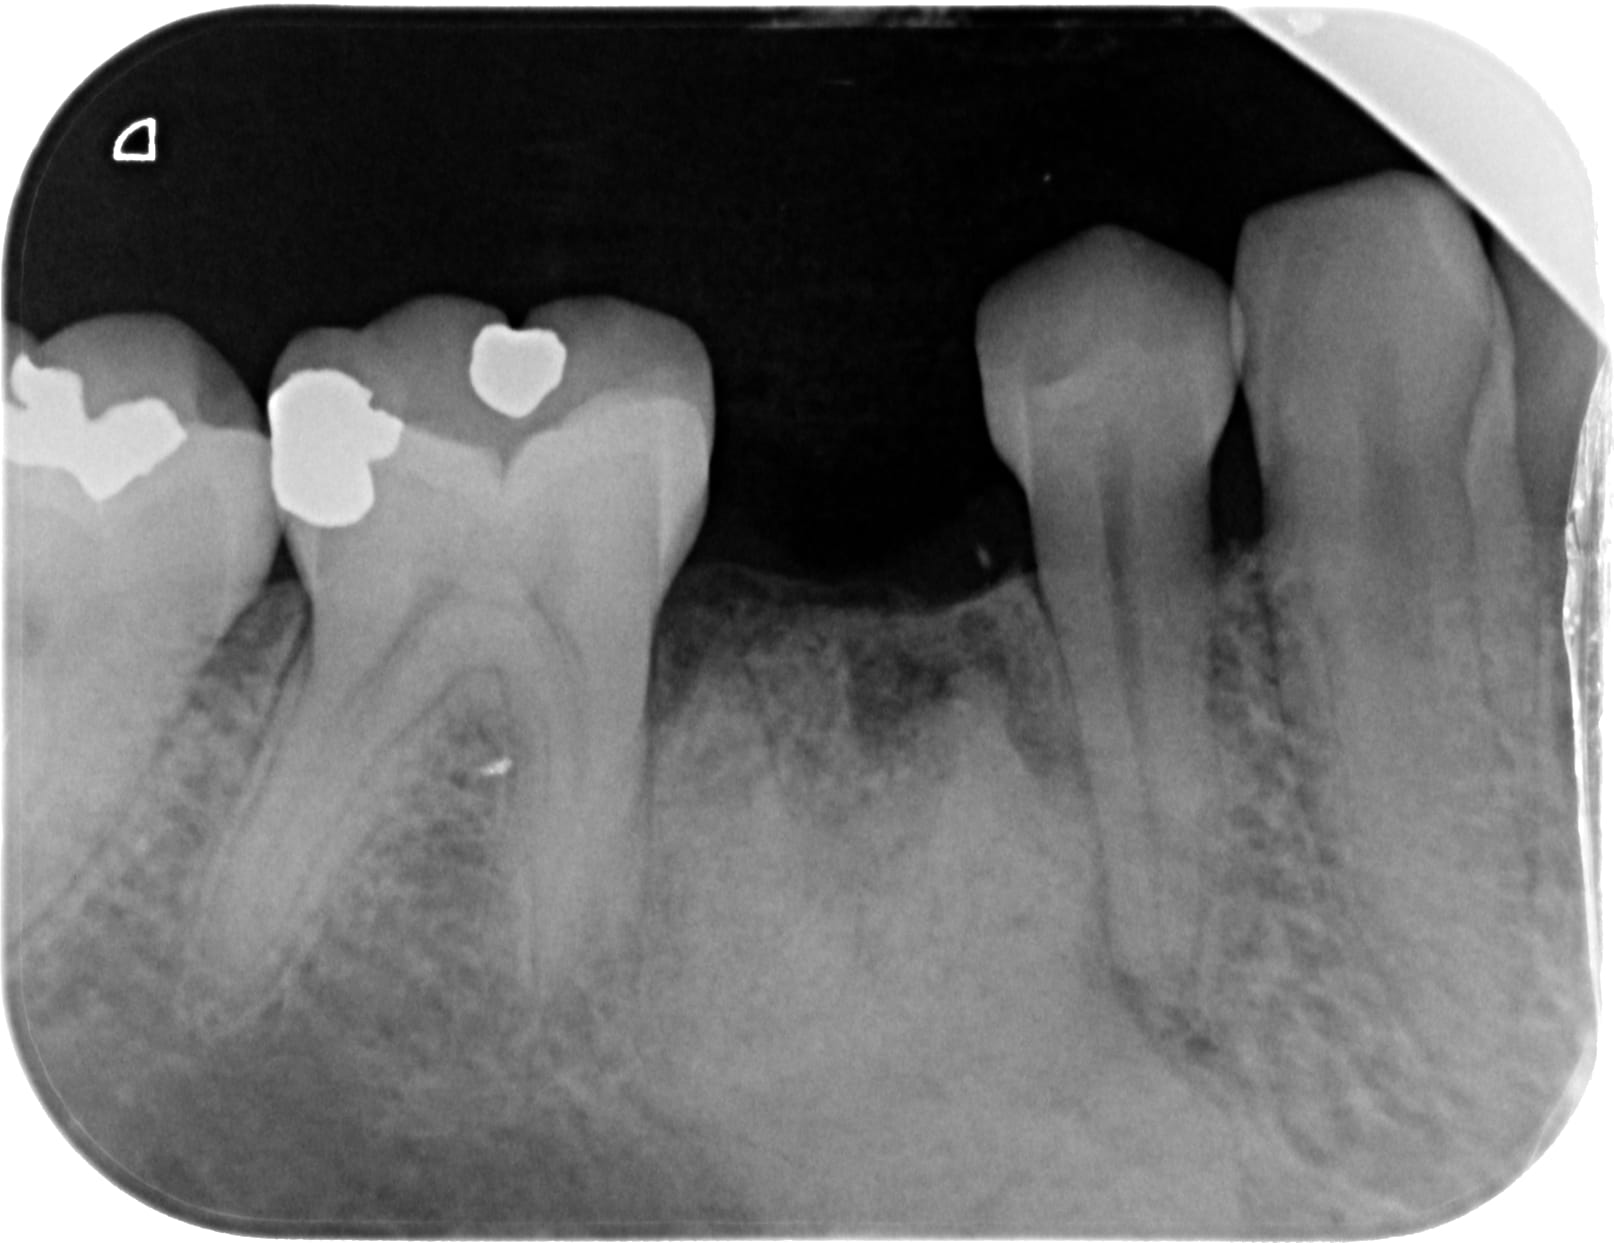

Ostéite condensante

Un éminent confrère implanto pourrait il me dire si on peut placer un implant dans une ostéite condensante, un an après avulsion?